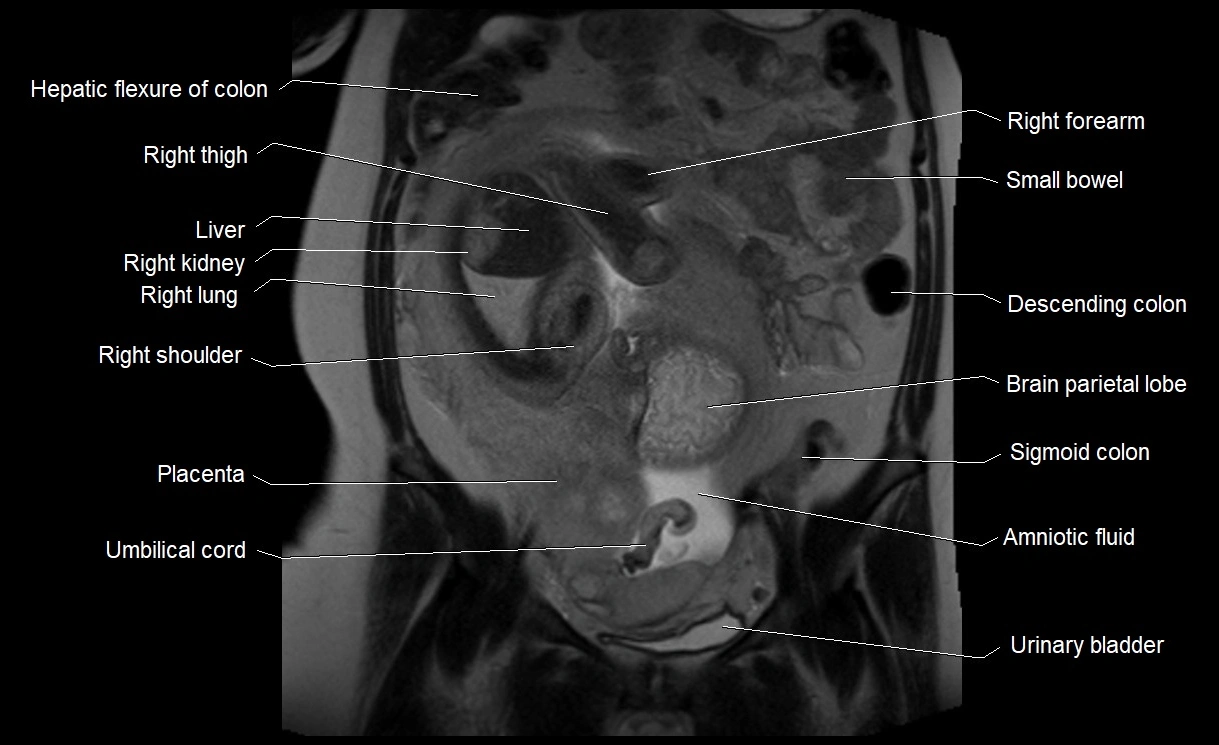

MRI Appearance

T2 HASTE (T2 GRE):

• Amniotic fluid shows very bright hyperintense signal

• Provides natural contrast against fetus and placenta

• Small particles (vernix) may appear as scattered hypointense foci within bright fluid

MRI image

image